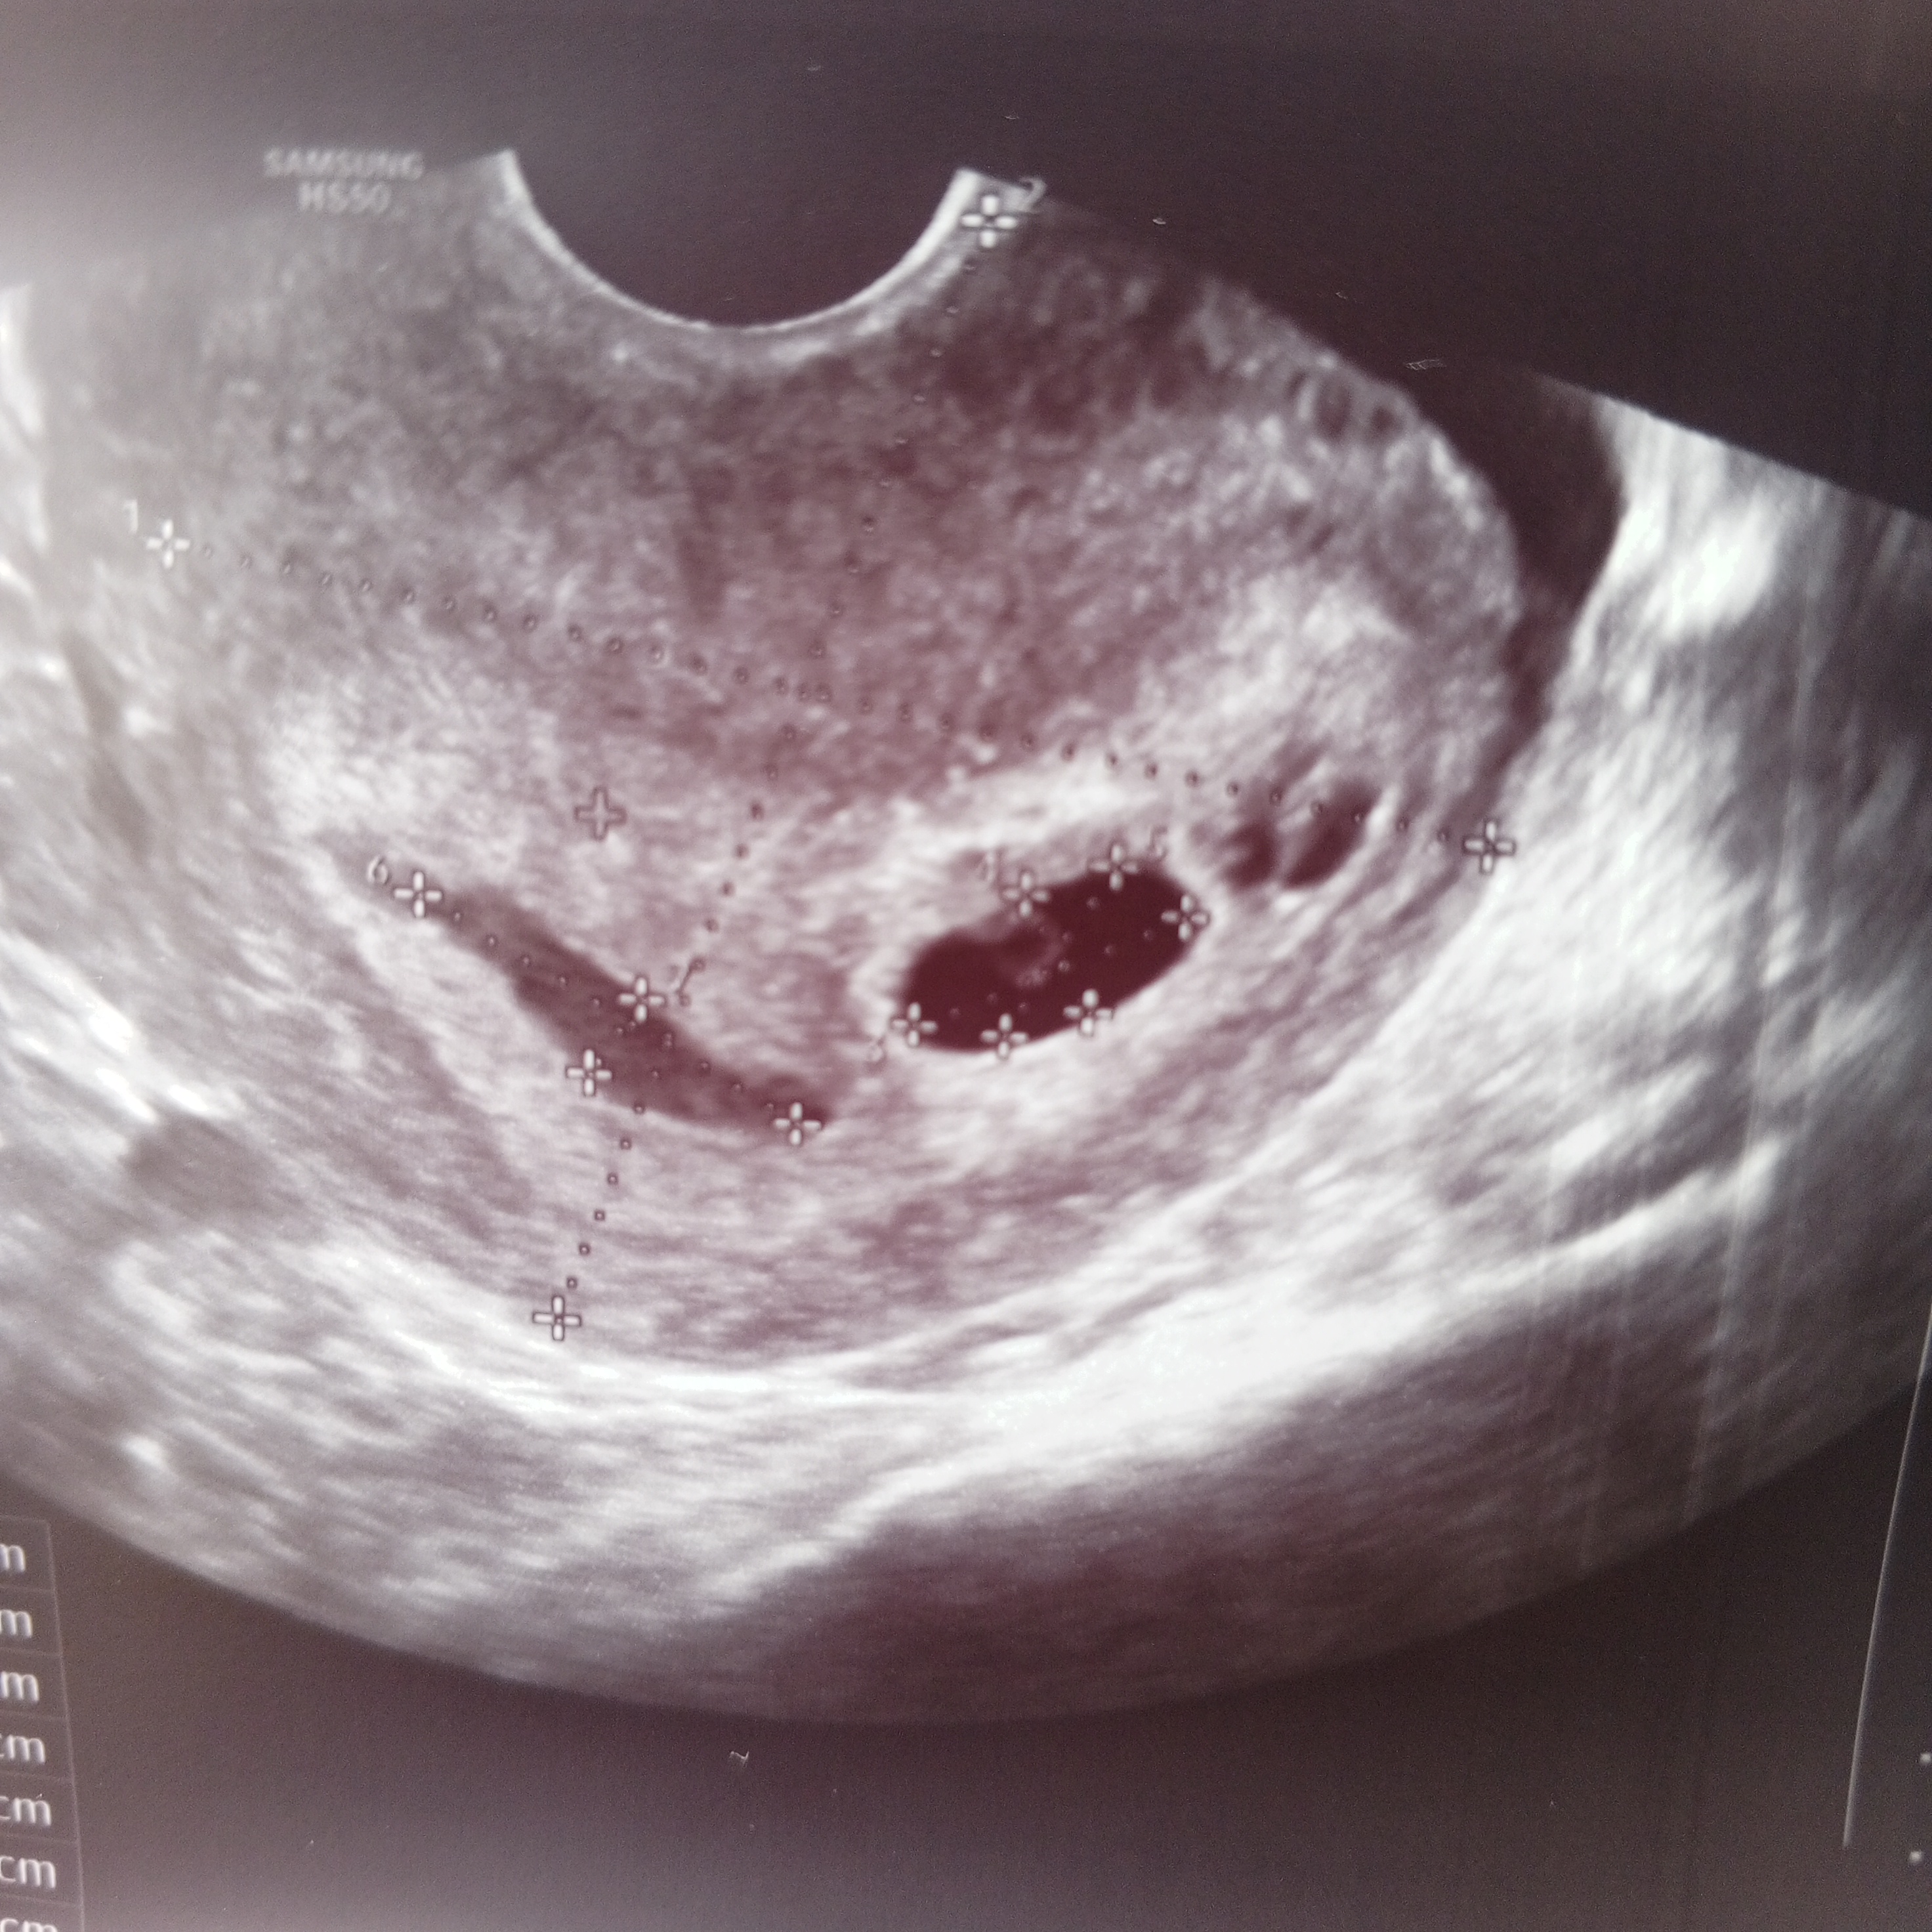

Узи на 20 и 29 дпо

Марина, за 9 дней, он должен был на 9 мм+- вырасти, я вот на фото посмотрела размер яйца там 1.37см Вот посмотрите, может мне не стоит туда больше не ходить Расст 3 это как раз размер пя Я вот думаю, может она и не захотела искать эмбриончика, говорила типа он прячется Изображение Изображение

Светлана , так здесь несколько размеров,не совсем понятно что и где, вообще считают свд(средний внутренний диаметр)пя,а не одну какую то сторону к примеру пя 12*8*6 свд будет 12+8+6 =26 и разделить на 3 и будет свд 8,6 мм

Марина, все хорошо, нашли эмбриона и сердцебиение 108 уд в мин, пя на 6.1 недель а эмбрион на 5.6 недель все хорошо кроме отслойки, прописали магний, где думали второе плодное яйцо это оказалось ещё одно отслойка, контроль через 10 дней и можно на учет становиться)